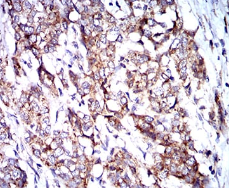

IHC    1/200 - 1/1000